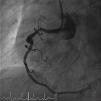

Homem, de 63 anos, recorre ao serviço de urgência do hospital mais próximo do local de férias por indisposição generalizada e dor mandibular com quatro horas de evolução, sendo diagnosticado enfarte agudo do miocárdio (EAM) da parede inferior. Já tinha antecedentes de EAM há quatro anos, em França, tendo colocado stents na coronária direita e circunflexa. Dado ser um centro sem capacidade de angioplastia, realizou fibrinólise nos primeiros 30 minutos, sendo depois transferido para centro com a mesma valência. A coronariografia revelou volumoso aneurisma no segmento médio da coronária direita em relação com porção proximal de stent, com trombo recanalizado (Figura 1). Foi tentada angioplastia para exclusão de aneurisma, mas não foi possível atravessar o stent com os fios guia utilizados. Ficou a ideia que a porção proximal do stent estaria ocluída, fazendo‐se o fluxo através da malha lateral. Dias depois fez‐se nova tentativa de angioplastia, apresentando aspeto de trombo organizado (Figura 2). Cruzou‐se a malha lateral do stent, mas não foi possível progredir um balão (Figura 3). A Figura 4 evidencia o resultado final.